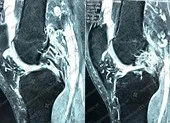

Sau khi chụp MRI và X quang, BS chẩn đoán ông N. bị đứt 3 dây chằng khớp gối trái. Đây là một trong những tổn thương nặng nề nhất ở khớp gối.

Các BS đã phẫu thuật nội soi tái tạo thành công tất cả 3 dây chằng, không gây tai biến. Hiện ông N. vận động được gối trái nhẹ nhàng, khớp gối cảm giác vững chắc, đi lại không còn bị sụm. Ông tiếp tục tập vật lý trị liệu để tăng cường biên độ vận động của khớp gối.